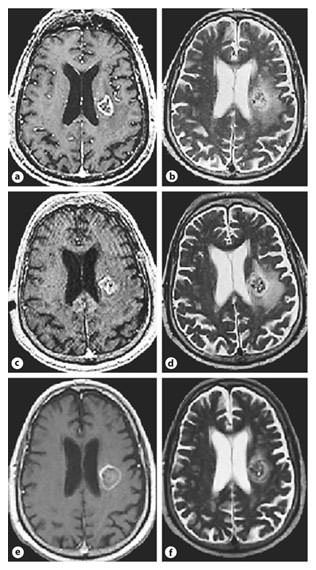

Once the appropriate thermal ablation zone was accomplished, an immediate series of MR sequences were obtained consisting of T1-weighted +/– contrast, T2-weighted, FLAIR, and diffusion sequences. Additional MRIs were obtained 24 hours after the procedure and at 7 weeks postoperatively.

The 24-hour postoperative MRI T1-weighted imaging revealed a central hyperintensity in the treatment location with faint peripheral contrast enhancement and T2/FLAIR prolongation within the lesion. The cross-sectional areas were used for objective calculations and obtained by the product of the largest perpendicular measurements in two places. Comparison of the preoperative and 24-hour postoperative scans showed no significant difference in the amount of surrounding edema. The 7-week T1 images revealed marginal increase in the diameter of the lesion, a minimal rim of enhancement, and markedly decreased edema on the T2 and FLAIR sequences (fig. 5).

a, b Pretreatment T1- and T2-weighted axial images. c, d Immediate posttreatment 24-hour T1 images reveal a decrease in the contrast enhancing rim with heterogeneous changes within the lesion and T2 MR images show a marginal increase in the degree of edema. e, f Follow-up imaging at 7 weeks, axial contrast T1 images revealing an increase in lesion size with a hypointense center and thin rim of enhancement, whereas the T2 images reveal a near total resolution of the perilesional edema.

a, b Pretreatment T1- and T2-weighted axial images. c, d Immediate posttreatment 24-hour T1 images reveal a decrease in the contrast enhancing rim with heterogeneous changes within the lesion and T2 MR images show a marginal increase in the degree of edema. e, f Follow-up imaging at 7 weeks, axial contrast T1 images revealing an increase in lesion size with a hypointense center and thin rim of enhancement, whereas the T2 images reveal a near total resolution of the perilesional edema.

Clinically the patient had word-finding difficulty and conduction dysphasia in the immediate postoperative period. These symptoms gradually improved and he was discharged 2 days following the procedure. His steroids were rapidly tapered off over 14 days, and he was closely followed for symptomatic worsening. On follow-up 7 weeks after the procedure, he remained neurologically stable, with near total resolution of symptoms and off of steroids.